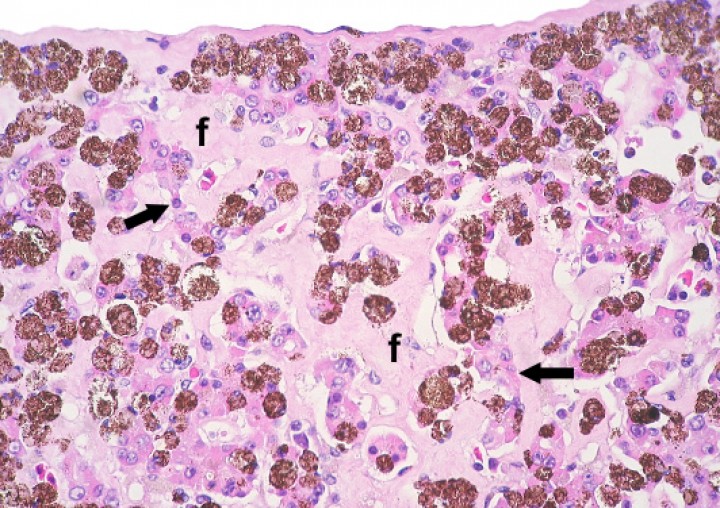

La mayoría de anfibios mostraban grados variables de melanización de diversos órganos, particularmente el hígado (Fig. 25). La cantidad y el tamaño de centros melanomacrofágicos en el hígado se consideraron excesivos en algunos pacientes y llegaron a remplazar casi completamente el parénquima hepático en casos esporádicos (Fig. 26). En uno de estos, una rana tomate, este proceso se acompañó de fibrosis portal leve (Fig. 27) e hiperplasia biliar.

<p>Hígado; rana tomate (<em>Dyscophus guineti)</em>. El tejido hepatocelular está parcialmente reemplazado por melanomacrófagos y fibrosis (f); los cordones de hepatocitos con frecuencia están atróficos (flechas) y también contienen melanina. Hematoxilina-eosina, x440.</p>

Hígado; rana tomate (Dyscophus guineti). El tejido hepatocelular está parcialmente reemplazado por melanomacrófagos y fibrosis (f); los cordones de hepatocitos con frecuencia están atróficos (flechas) y también contienen melanina. Hematoxilina-eosina, x440.